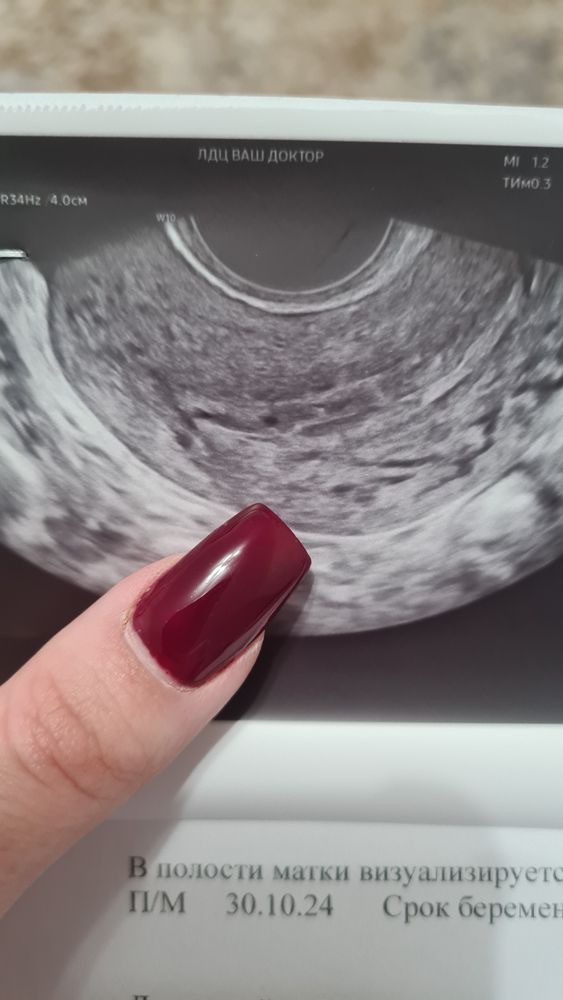

Задержка менструации и отрицательный результат тестов и ХГЧ при возможном наличии ПЯ

Нет, это не плодное яйцо. У меня тоже была подобная история - на следующий день начались месячные. Это типа сосуда или что-то такое.

Это не ПЯ, переделайте узи в другом месте

Вы не беременна, по вашим показателям. На узи не пя